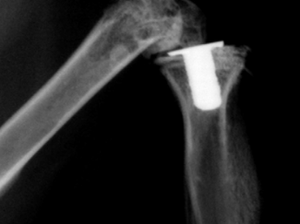

骨端が分離した時には、骨端板の損傷は避けられませんが、ていねいな操作で整復して、損傷の拡大を防ぎ、1~数本のKirschnerワイヤーまたは海綿質用ネジで固定します。